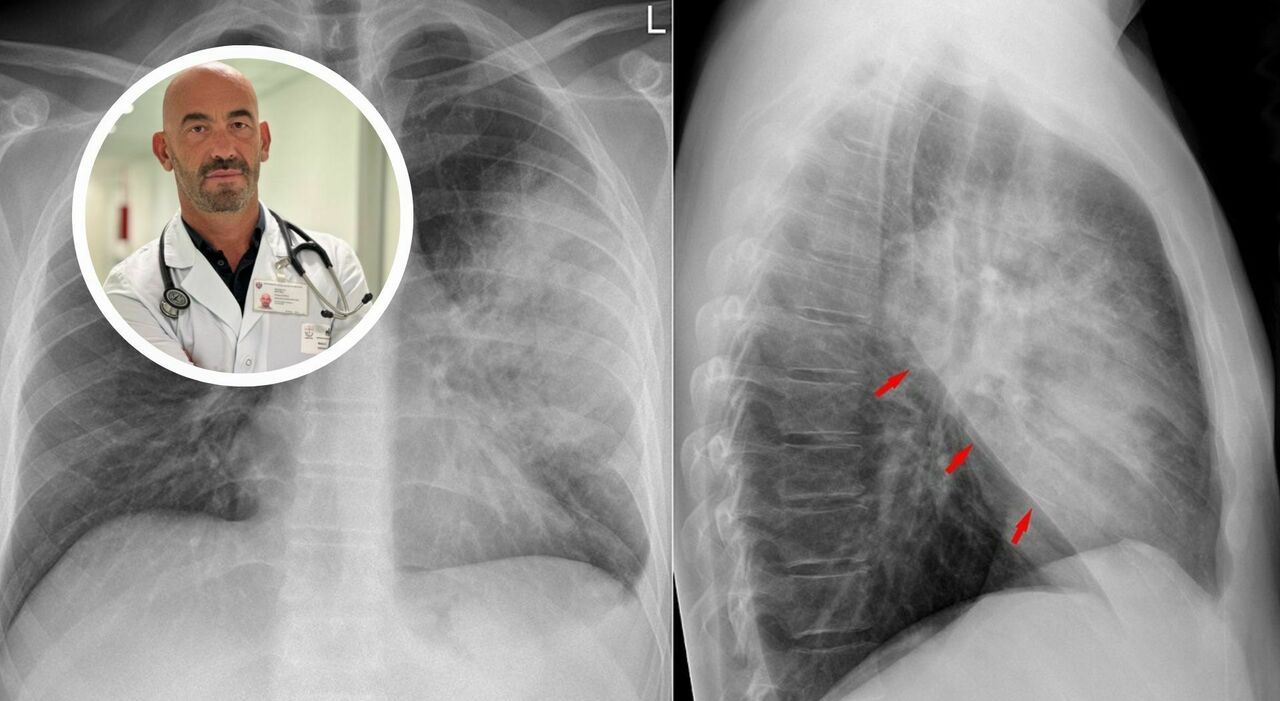

«I nostri ospedali sono già oggi pieni di casi di polmonite», avverte Matteo Bassetti, direttore Malattie infettive dell’ospedale policlinico San Martino di Genova. Ogni anno in Italia ci sono almeno 150mila ricoveri e 9mila i decessi. Ma i dati “importanti” dell’andamento dell’influenza (e altri virus) in Australia non fa ben sperare per quest’anno. Anche perché alcuni recenti casi noti, come per la morte del maestro Peppe Vessicchio (per la forma interstiziale) o per il ricovero dell’allenatore del Bologna Vincenzo Italiano, hanno riportato alta l’attenzione. Anche se, fortunatamente, in Italia la mortalità è una delle più basse d’Europa. Vediamo insieme cause, sintomi e come riconoscere la polmonite con il dottor Bassetti.